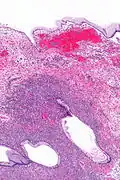

| Micrograph showing a mucinous cystadenoma of the ovary. H&E stain. | |

Mucinous cystadenoma is a benign cystic tumor lined by a mucinous epithelium. It is a type of cystic adenoma (cystadenoma).

Mucinous cystadenomas make up 15–20% of all ovarian tumors. They often become very large and can extend up into the abdomen.

These tumors are usually evaluated using ultrasound, CT scan, or MRI. Findings on imaging studies are nonspecific. These ovarian tumors are usually multi-septated, cystic masses with thin walls. They also contain varying amounts of solid tissue which consists of proliferating stromal tissue, papillae, or malignant tumor cells.

Benign mucinous cystadenomas compose 80% of mucinous ovarian tumors[2] and 20–25% of benign ovarian tumors overall. The peak incidence occurs between 30 and 50 years of age. Benign tumors are bilateral in 5–10% of cases.